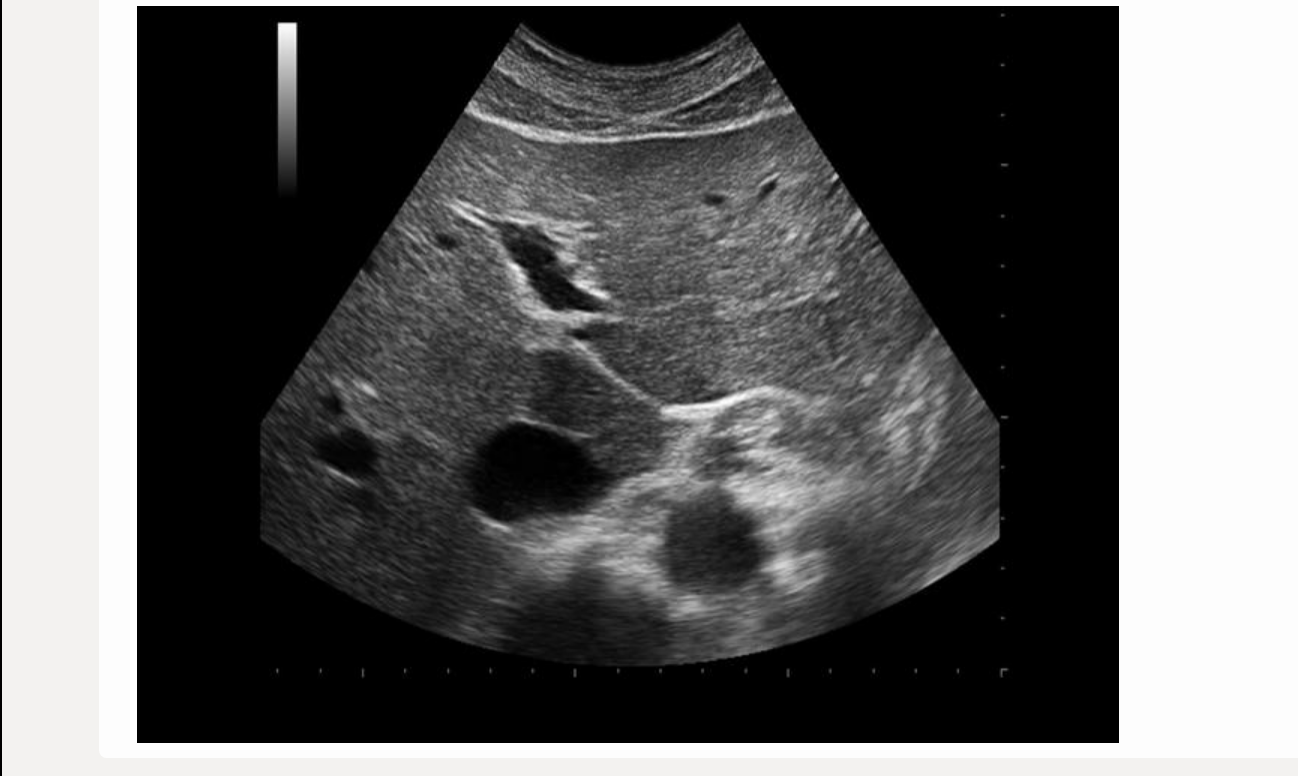

![<p>find IVC </p><p>.</p><p>[IVC = posterior to panc head]</p>](https://knowt-user-attachments.s3.amazonaws.com/61e93537-e382-4129-8353-88053b5a2e79.png)

find IVC

[IVC = posterior to panc head]

IVC = posterior to panc head